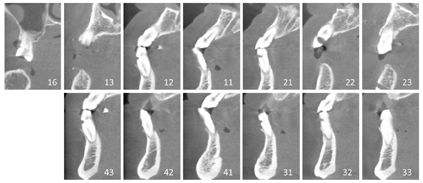

14、15、24-26、34-37、44-47缺失,缺牙区牙槽嵴丰满度一般;16牙探及并可穿通根分叉,但未见根分叉暴露,13残根,11近中颈部、23远中龋坏,33、43牙颈部缺损;31、41松动Ⅲ度,11、12、32、42松动Ⅱ度,16、21-23、33、43松动Ⅰ度,全口散在间隙。全口卫生状况一般,探诊深度5~8 mm,附着丧失6~9 mm,牙龈水肿,探针出血,可探及龈下结石。咬合关系欠佳,口角下垂,面下1/3高度降低,鼻唇角接近90°。上唇活动度较小,中位笑线(图1)。颞下颌关节检查无明显异常,开口型正常,开口度三横指。放射学检查:术前全景片显示13残根,16牙根尖牙槽骨吸收,11、23牙远中颈部见低密度影,余留牙牙周膜间隙增宽,周围牙槽骨水平吸收至根尖1/3-1/2(图2)。术前CBCT截图显示13牙残根,12、21、22、31、32、33、43牙颈部见不同程度楔状缺损。31、41、42牙周围牙槽骨水平吸收至根尖1/3,16、12、11、21-23、32、33、43牙牙周膜增宽,周围牙槽骨水平吸收至根尖1/2不等(图3)。